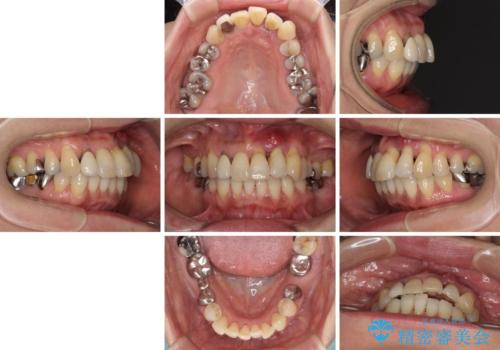

- 前歯の歯肉の腫れを気にして来院された患者様です。

前歯のみならず、奥歯の銀歯や下顎前歯のデコボコなど、色々と気になる部分を治したいとのことでした。

前歯は抜歯が必要であったので、抜歯を行い、その後歯肉移植をおこなった上でオールセラミックブリッジによる補綴治療を行うこととしました。

下顎と上顎臼歯部については矯正治療を行い、奥歯の欠損部位はオールセラミックブリッジを、その他の銀歯はセラミックインレーなどにより治療を行うこととしました。